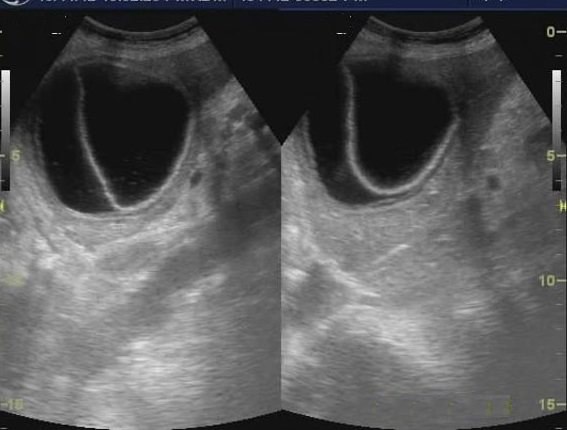

Áspect echographique d'une

abces du foie : C'est une masse ovalaire hypoechogen

en cloisone et a paroie hyperechogen

.Sans renfocement ou renforcement legere de

ascoustique posterieure |

Image echographique

d'une abces du foie lobe droit : Aspect

multilobulaire a hypoechogene avec paroi tres

epaisse |